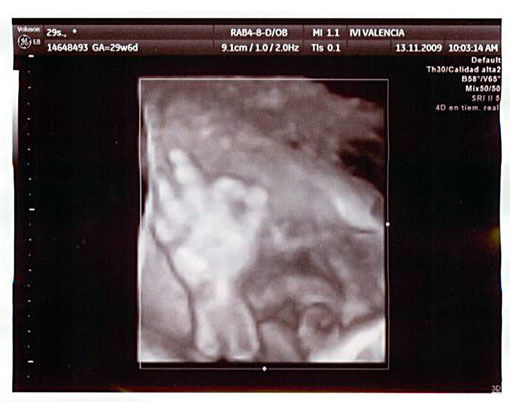

Hace unos días os enseñé una ecografía en la que un bebé hacía con los dedos el signo de "victoria". A raíz de dicha entrada, Ismael, un lector del blog, nos comentó que en la ecografía realizada a su futuro hijo, hace ahora un par de semanas, les dijo que "todo está ok".

Gonzalo, que es como se llamará el niño, decidió enviar a sus padres, en esta ecografía realizada en la semana 31 de gestación, un mensaje de tranquilidad en plan "aquí dentro todo está bien", "no os preocupéis por mí, que estoy de fábula" o "todo bien, comandante".

Gracias a Ismael y Macarena, los padres de Gonzalo, por enviarnos esta ecografía tan curiosa. Está claro que con las ecografías 4D se pueden captar gestos de lo más curiosos que con otros medios habrían pasado desapercibidos.